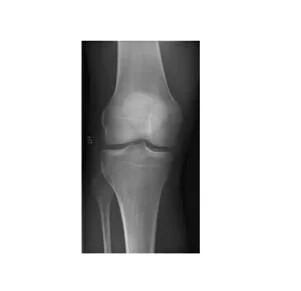

What's in an X-ray ?

Images for your osteoarthritis are often done unnecessarily. In the first instance, an X-Ray of your joint such as the knee or hip may not be required. Health professionals such as physiotherapists can diagnose osteoarthritis from your examination and questions we ask you. So when is the right time to get an X-Ray or an MRI of your joint ? What do your imaging findings really mean ?